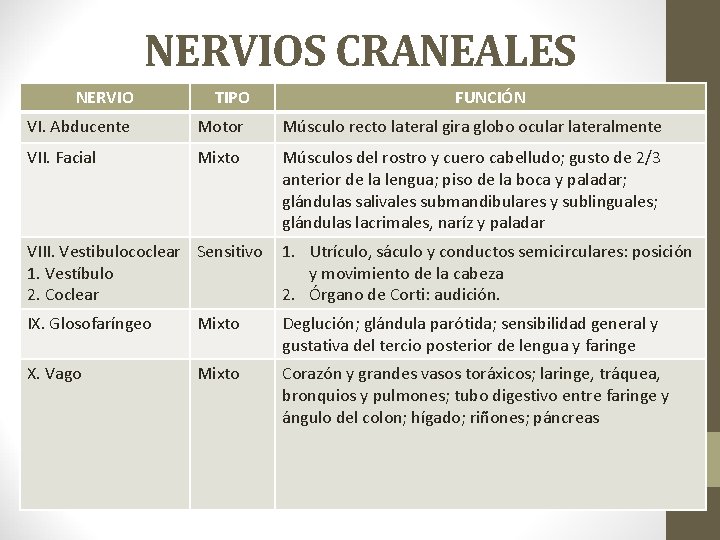

NERVIOS CRANEALES NERVIO TIPO FUNCIÓN VI. Abducente Motor Músculo recto lateral gira globo ocular lateralmente VII. Facial Mixto Músculos del rostro y cuero cabelludo; gusto de 2/3 anterior de la lengua; piso de la boca y paladar; glándulas salivales submandibulares y sublinguales; glándulas lacrimales, naríz y paladar VIII. Vestibulococlear Sensitivo 1. Vestíbulo 2. Coclear 1. Utrículo, sáculo y conductos semicirculares: posición y movimiento de la cabeza 2. Órgano de Corti: audición. IX. Glosofaríngeo Mixto Deglución; glándula parótida; sensibilidad general y gustativa del tercio posterior de lengua y faringe X. Vago Mixto Corazón y grandes vasos toráxicos; laringe, tráquea, bronquios y pulmones; tubo digestivo entre faringe y ángulo del colon; hígado; riñones; páncreas

NERVIOS CRANEALES NERVIO TIPO FUNCIÓN XI. Accesorio 1. Raíz craneal 2. Raíz espinal Motor 1. Músculos del paladar blando, de la faringe y de la laringe 2. Músculos esternocleidomastoídeo y trapecio XII. Hipogloso Motor Músculos de la lengua (excepto el palatogloso) que controlan su forma y movimiento